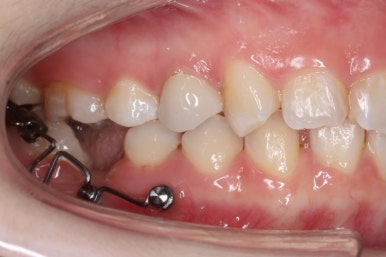

초진 때의 입안 모습입니다.

앞니는 고른 편이였으나 군데군데 틈새가 있었습니다. 약간 삐뚠 모습도 보이지만 환자분께서 개선을 하고자 했던 부분은 아래쪽 어금니 1개가 없는 자리였습니다.

장치를 붙인 모습입니다.

개선을 하고자 하는 어금니에만 장치를 붙였고 다른 치아는 움직이지 않아야 하기 때문에 강한 지지대가 되어야 할 부분에 미니스크류를 식립했습니다.